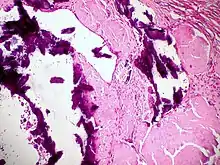

Dystrophic calcification

Dystrophic calcification (DC) is the calcification occurring in degenerated or necrotic tissue, as in hyalinized scars, degenerated foci in leiomyomas, and caseous nodules. This occurs as a reaction to tissue damage,[1] including as a consequence of medical device implantation. Dystrophic calcification can occur even if the amount of calcium in the blood is not elevated (a systemic mineral imbalance would elevate calcium levels in the blood and all tissues) and cause metastatic calcification. Basophilic calcium salt deposits aggregate, first in the mitochondria, then progressively throughout the cell. These calcifications are an indication of previous microscopic cell injury, occurring in areas of cell necrosis when activated phosphatases bind calcium ions to phospholipids in the membrane.